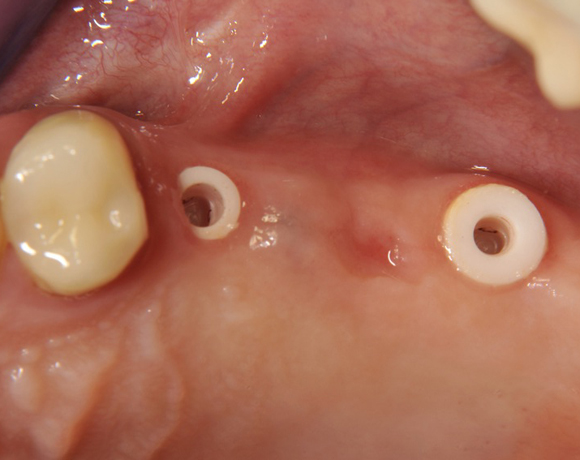

Im vorliegenden Patientenfall wurden für die Zähne 25 und 27 jeweils ein Implantat gesetzt. Nachdem die Implantate eingeheilt waren, wurde 25 – 27 mit einer Brücke versorgt.

Der prothetische Teil